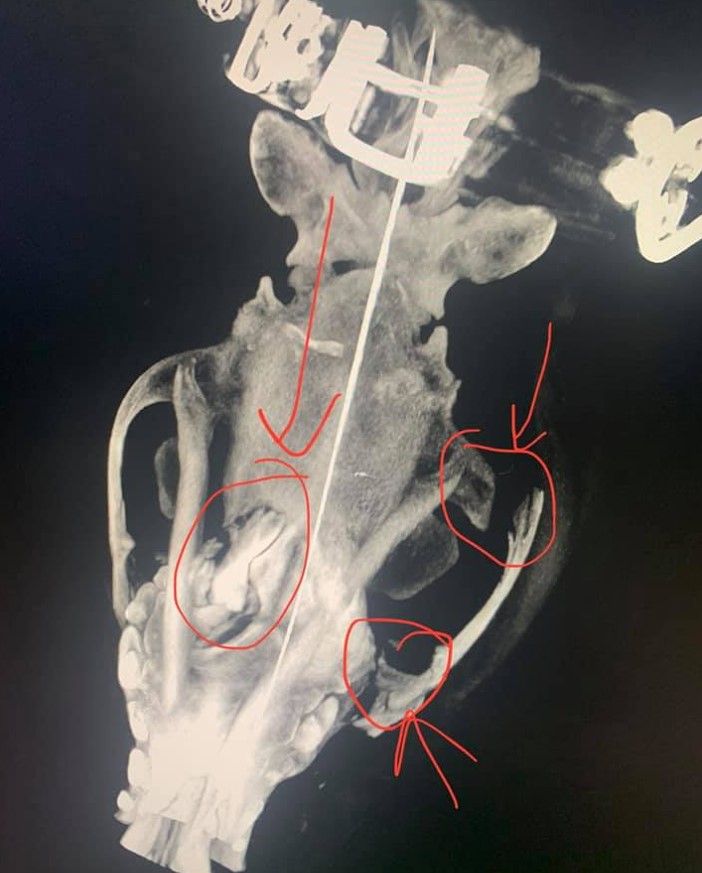

Как пишет hromadske, Елена Корень, которая помогает животным, рассказала, что инцидент произошел в селе Холодная Балка. Собака якобы впервые убежала от хозяина. После избиения у нее проломлен череп и перелом челюсти, собаку ввели в искусственную кому.